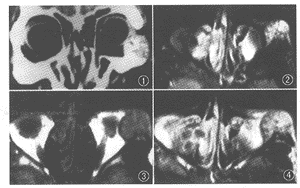

3、MRI表現

動脈瘤樣骨囊腫(2)病灶主體於T1WI上呈低信號,T2WI呈高信號,腔內間隔均呈低信號。部分病例T2WI上病灶內出現液-液平面,此為本症的特徵性表現,上部高信號區代表漿液而下部低信號區代表含鐵血黃素沉積。

(3)病灶周邊骨殼呈圓圈樣低信號,一般完整,邊緣清晰。

(4)增強掃描:病灶內間隔強化。MRI影像ABC的檢查也有特徵性。因病灶分隔成多數含血的竇腔,所以表現為T1WI呈低等信號,T2WI呈多發不均勻高信號,其間可見纖細的低信號間隔。Munk研究,隨T1WI加重,病灶信號強度增高,或者病例出現T2WI可見液—液平面者,上方為高信號(內含去氧血紅蛋白的液體),下方為低信號(內有含鐵血黃素),強烈提示ABC的診斷。另外病灶中心活動度低,增強掃描MRI可以顯示病灶邊緣性輕度強化,強化特點比CT靈敏度高。